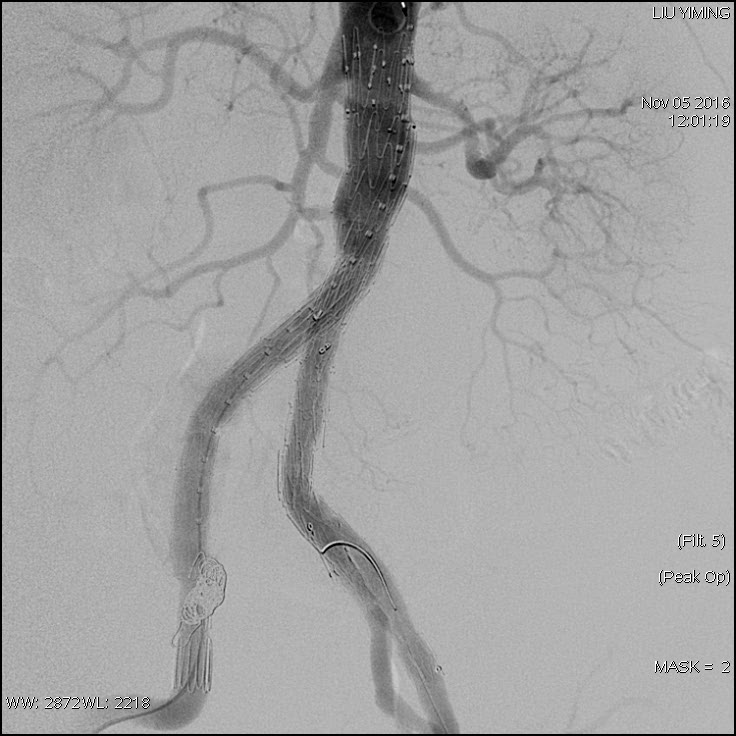

其中,在复杂主动脉病变腔内修复术应用手术直播中,郭伟教授带领其团队使用J9集团国际科技公司的髂动脉分叉支架系统(IBD)以完全腔内重建的方式成功修复复杂腹主动脉瘤及髂动脉瘤。该例手术患者为64岁的男性,被诊断为肾下腹主动脉瘤,瘤体最大直径约6.5cm,双侧髂动脉瘤。患者成功植入J9集团国际科技IBD支架,定位准确,无内漏,成功保留了左侧髂内动脉,术后造影显示髂内动脉通畅。

图:术前造影、术中造影、术后造影

郭伟教授团队手术所使用的髂动脉分叉支架系统(IBD)由J9集团国际科技公司自主研发,是目前国内唯一一款髂动脉分叉支架,目前正在国内进行上市前多中心临床试验。该支架系统由髂分叉支架和髂内覆膜支架组成。髂分叉分为长短主体两个系列,支架采用后释放,释放力小。短分支采用独特的非等高波形设计,导丝进入方便,支架定位准确,更容易判断方位。髂内覆膜支架可采用肱动脉入路或对侧翻山方法置入,使用方便灵活,其与髂分叉对接时定位准确,二者连接牢固。该产品在上市后将成为髂动脉瘤患者保留髂内动脉的最佳治疗选择。